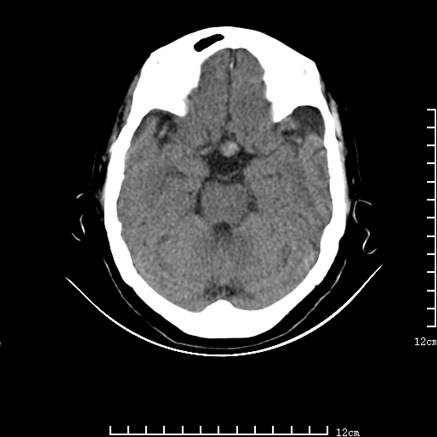

标题: V0514:女,72岁,偶有头晕,自诉记忆力减退,来诊。 [打印本页]

标题: V0514:女,72岁,偶有头晕,自诉记忆力减退,来诊。

是拉特可囊肿(rathke cyst)吗?

考虑垂体瘤可能性大

1、考虑垂体腺瘤。

垂体腺瘤可能性大!另:轻度脑萎缩!

考虑垂体腺瘤可能性大。脑萎缩。

考虑垂体腺瘤可能性大。脑萎缩。  建议mri 检查

垂体瘤,建议mri

垂体腺瘤